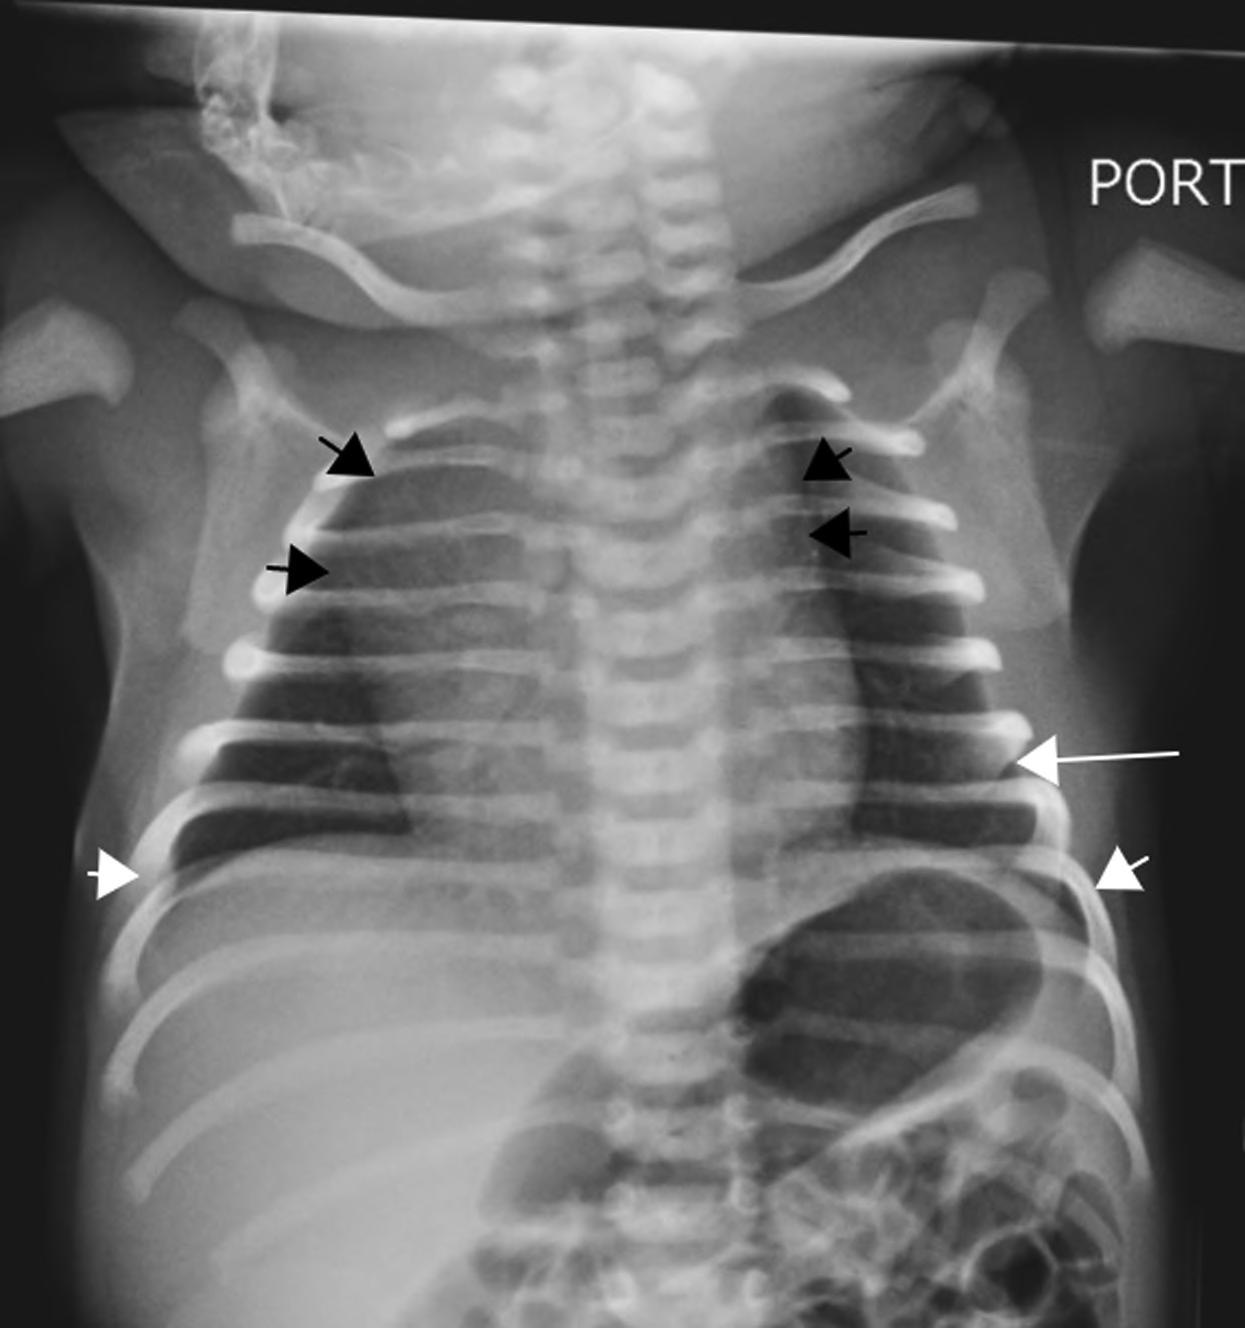

2.2. A normal neonatal chest radiograph. Note the sharp costophrenic angles (small white arrows), the aerated lung extending below the level of the 6th rib anteriorly (long white arrow), and the contour of a normal for age thymus expanding the superior mediastinum (small black arrows).

FIGURE

The following should be evaluated systematically when approaching any neonatal CXR:

• Symmetric aeration—determined by visualization of the 6th rib anteriorly and 8th rib posteriorly

• Pulmonary vasculature—should be visible in the central 2/3 of the lungs

• Hemidiaphragm(s)—dome shaped with sharp costophrenic angles

• Cardiothoracic ratio can be up to 60% (0.6) in neonates. Cardiothoracic ratio is the ratio of maximal horizontal cardiac diameter to maximal horizontal thoracic diameter on a frontal CXR.

• Thymus gland

• Don’t forget to evaluate the upper abdomen, bones, and soft tissues!